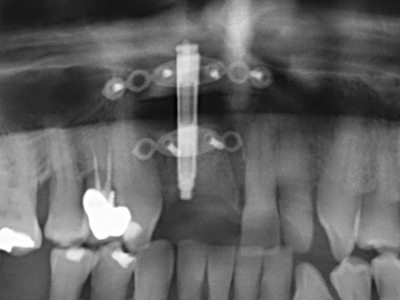

Indikation: Bone Splitting

Knochengewebe ist nicht nur rein mineralisch, sondern auch in wesentlichen Anteilen aus Kollagenfasern aufgebaut. Dies gewährleistet neben einer guten Druckfestigkeit eine gewisse Flexibilität, welche für die Durchführung von Augmentationen genutzt werden kann. Bei der klassischen Expansionsplastik im Sinne eines Bone Splittings wird der atrophierte Kieferkamm in seiner Längsachse gespalten und nach Erreichen einer ausreichenden Osteotomietiefe vorsichtig aufgedehnt (Abb. 13-16), idealerweise ohne den Kiefer wesentlich zu deperiostieren (Brugnami, Caiazzo et al. 2014, Stricker, Fleiner et al. 2014). Bewährt haben sich Schrauben- und Plattensysteme mit zunehmender Expansionsdistanz, um die beiden Knochenlamellen unterhalb der Bruchschwelle voneinander zu distanzieren. In der Regel werden Restknochenbreiten von mindestens 3-4 mm gefordert (Chiapasco, Zaniboni et al. 2006), um eine ausreichende Flexibilität und knöcherne Bedeckung der einzubringenden Implantate zu gewährleisten. Ggf. kann eine ein- oder beidseitige vertikale Entlastungsosteotomie die Flexibilität verbessern. Als Alternative zur klassischen Technik wurde eine Kombination mit weiteren augmentativen Techniken vor allem auf der bukkalen Seite beschrieben.

Mittels Piezosägen erfolgt die Anlage des Splittings besonders schonend und ohne wesentliche Dimensionsverluste, so dass sich keine signifikanten Unterschiede von Implantaten im gesplitteten Kiefer im Vergleich zum nicht defizitären Alveolarkamm gezeigt haben (Chiapasco, Zaniboni et al. 2006, Danza, Guidi et al. 2009). Gerade beim lokal begrenzten und tiefen Splitting ist jedoch stets auf eine ausreichende Wasserkühlung zu achten, um thermische Belastungen in den apikalen Osteotomiebereichen zu vermeiden.